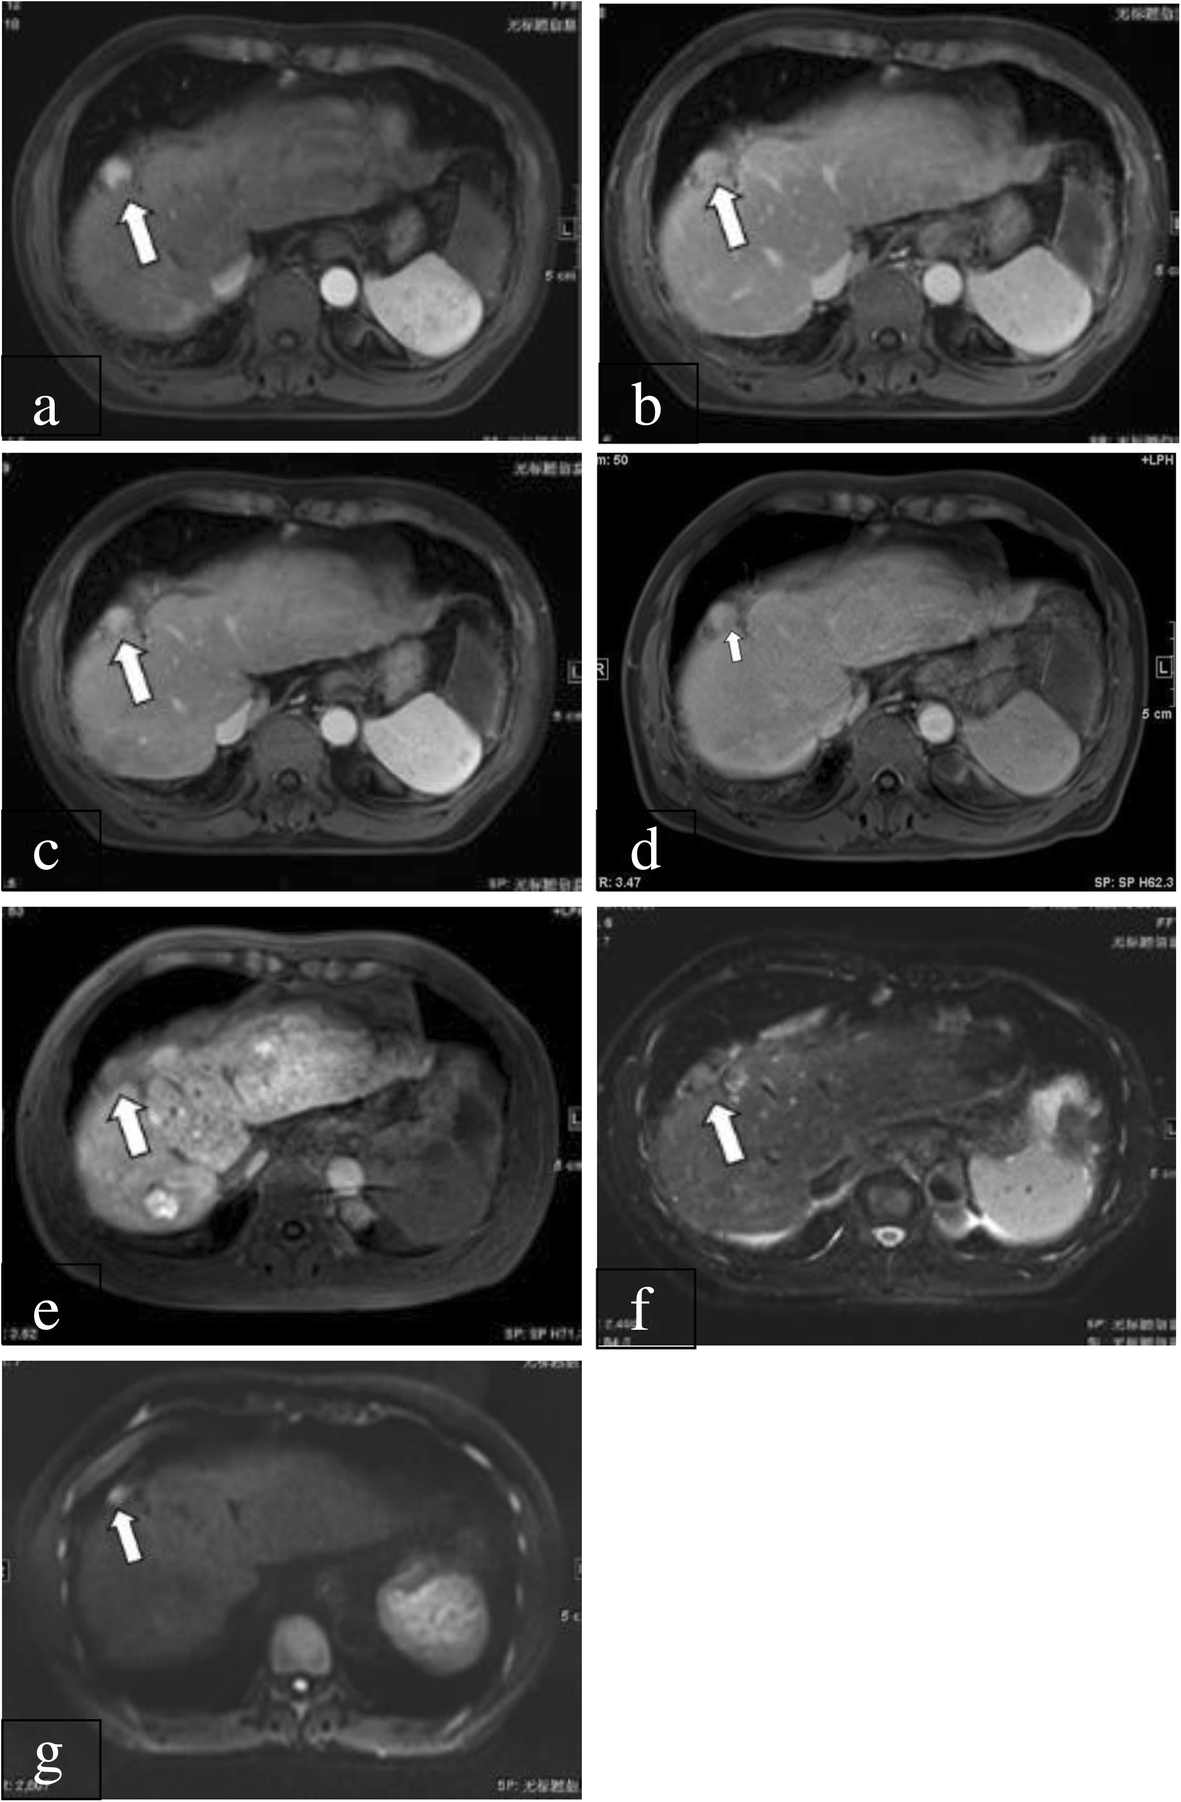

Fig. 1

A 57-year-old male patient with HCC confirmed by surgery. a: On gadopentetate dimeglumine-enhanced 1.5-T MRI, there was a 20-mm nodule (arrow) showing arterial enhancement. b: During the PVP, the nodule (arrow) was isointense (no washout). c: During the delayed phase, the nodule (arrow) also showed no washout sign. d: Three days later, the patient underwent gadoxetic acid-enhanced 1.5-T MRI. During the PVP, the nodule (arrow) showed was isointense and hypointense. e: During the HBP, the nodule (arrow) was hypointense. f: On T2-weighted imaging, the nodule (arrow) was moderately hyperintense. g: On diffusion-weighted imaging, the nodule (arrow) showed restricted diffusion. Therefore, the preliminary LI-RADS category based on the major imaging features and considering the ancillary features was LR-4 using gadopentetate dimeglumine-enhanced 1.5-T MRI. After taking into account the sign on hepatobiliary phase, the LI-RADS category was upgraded to LR-5